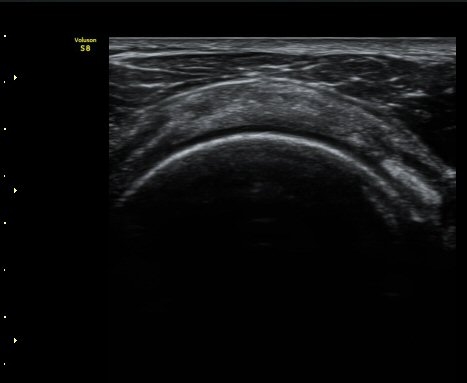

¼ö¾×Àú·ù°¡ °üÂûµÈ´Ù(±×¸² 1, 2). °ß°©ÇÏ±Ù°Ç Á¾´Ü¸é°Ë»ç¿¡¼­ °ß°©ÇϱٰÇÀÇ °üÀý³»ºÎÀ§(±×¸² 3)

¿Í ¼Ò°áÀý »óºÎ(±×¸² 4)¿¡¼­ ƯÀÌ ¼Ò°ßÀ» º¸ÀÌÁö ¾Ê´Â´Ù.